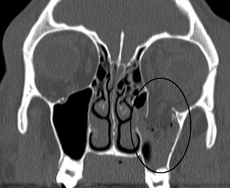

- Obtain orbital CT as initial study if significant clinical findings

- Look for teardrop sign on coronal view of CT

- Shows cloudy maxillary sinus representing blood, fluid or tissue